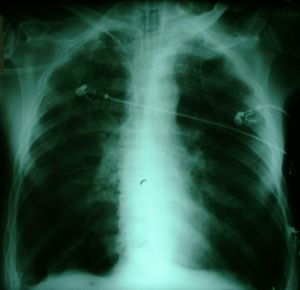

After Recruitment

Arterial blood gas 19:00 23/10/1999 Fi0 2=60%

pH=7.45 pCO 2=34 pO 2= 182 Saturation 99.5

The above X-rays illustrate one of the most dramatic and successful

maneuvers you can perform in Intensive Care. The patient whose X-rays

are shown is a man in his sixties who had surgery for malignancy,

and subsequent to multiple complications including a deep vein

thrombosis, pulmonary embolism, and perineal sepsis, developed hypoxaemia

and bilateral pulmonary infiltrates, in the absence of clinical evidence of

elevated left atrial pressure. A recruitment maneuver produced

substantial improvement in his oxygenation, which was maintained.

By 23:00 on the same day he was weaned down to an FiO2 of

35% with the following blood gas:

pH=7.39 pCO2=35 pO2=69 Saturation 94

The above patient was selected as an example of a mild to moderate

success. In many cases, recruitment is even more dramatic (We felt

that if we showed you such cases, you wouldn't believe us)!